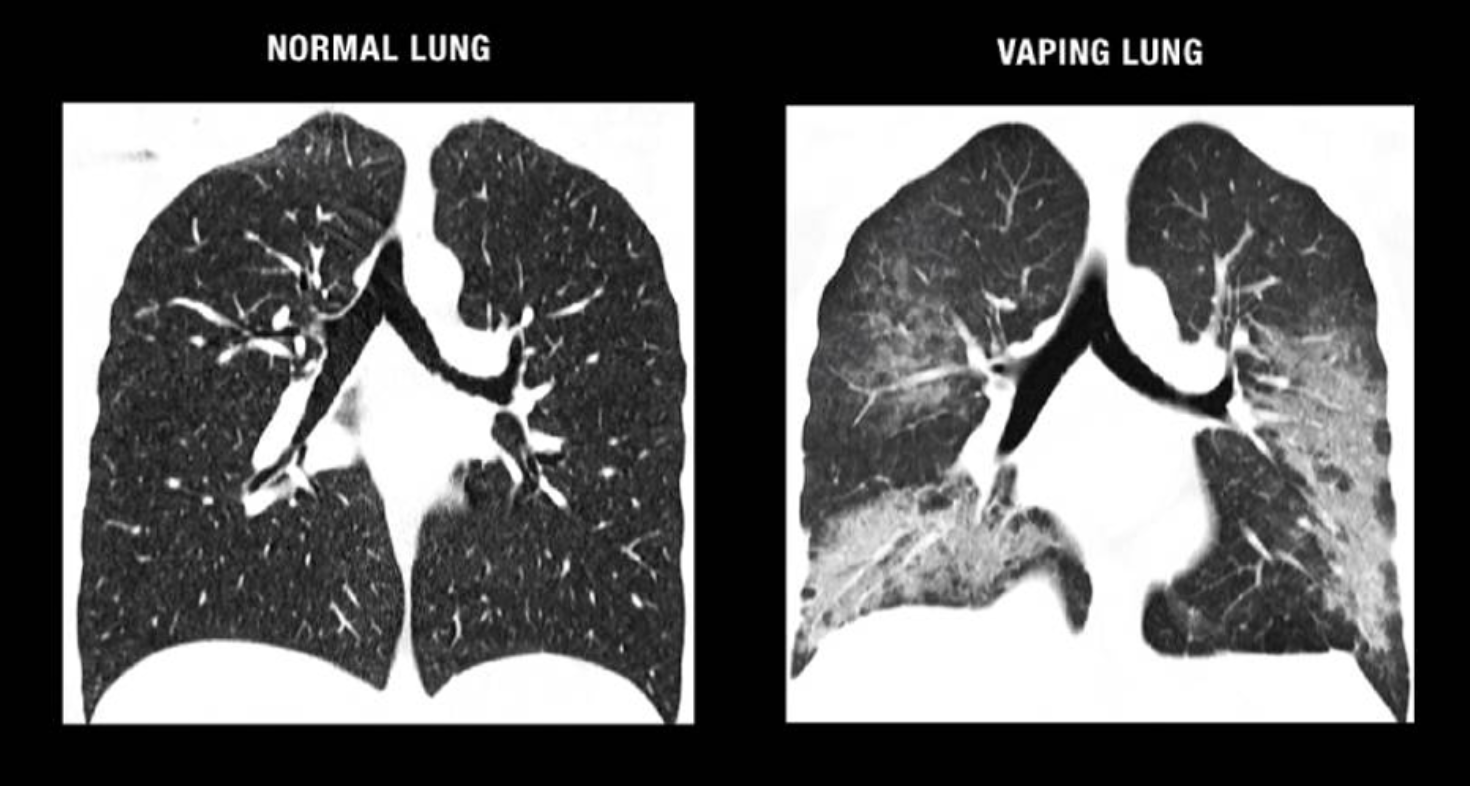

La EVALI se caracteriza según los criterios diagnósticos propuestos por la CDC en: Historial de uso de CigE en los últimos 90 días, infiltrados pulmonares en una radiografía de tórax y ausencia de hallazgos infecciosos pulmonares39.

Figura 7: Comparativa tomografía de paciente sin vs con EVALI. (Imagen tomada de Holly Area Schools)40.

Se ha reportado que aquellos pacientes diagnosticados con EVALI muestran hallazgos patológicos consistentes con lesión pulmonar aguda que puede incluir neumonitis fibrinosa, daño alveolar difuso y neumonía organizativa. Los productos de vapeo con THC se han asociado principalmente al desarrollo de esta patología, sin embargo, hasta el 15% de los pacientes con diagnóstico de EVALI reportaron usar únicamente productos de vapeo con nicotina, por lo que el mecanismo de lesión permanece poco comprendido41,42.